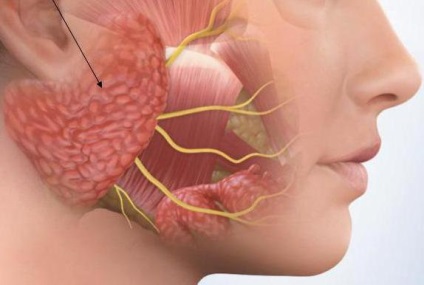

Mielőtt mondani arról, hogy a kezelés sialoadenita, azt kell mondani, hogy vannak többféle nyálmirigyek az emberi szervezetben. Ha a gyulladás egyikük, nyugodtan főzni sialoadenita fejlődését.

Fültőmirigy, submandibularis és a nyelv alatti nyálmirigyek hozzájárulnak az ilyen specifikus kiválasztást, nyál. Belép a szája olyan speciális csatornákat. A fő funkciója a titok az, hogy biztosítsák a normális és egészséges áramlását emésztési folyamatot.

sialadenitis kialakulhat valamilyen okból (a kezelés a betegség később ismertetjük)? A szakértők szerint, leggyakrabban emberi gyulladt parotisban. Az orvosok azonban azt sugallják, több oka is a fejlesztés a kóros állapotot.